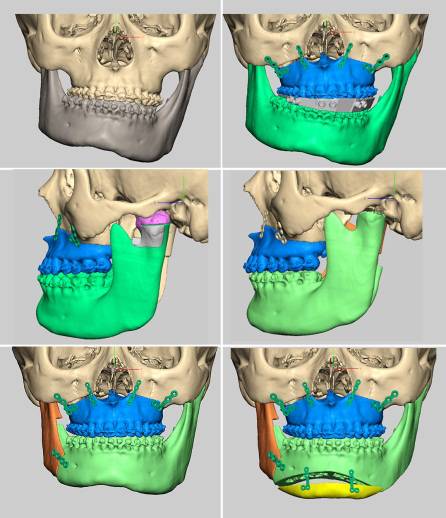

什么是计算机辅助正颌外科手术设计?

目前可使用软件将螺旋CT或锥束CT等影像学数据经计算机处理后,三维重建患者的颌骨形态,辅助牙颌面畸形的诊断,模拟手术截骨、移动、固定等,并制作相应的数字化导板辅助术中手术实施。同时因为计算机辅助手术设计可以更为直观的观察到术后颌骨的位置,更方便患者直观的了解手术效果,理解手术方案,便于医患沟通沟通。

(摘自“第四章第三节 牙颌面畸形治疗计划”)

计算机辅助正颌外科手术设计